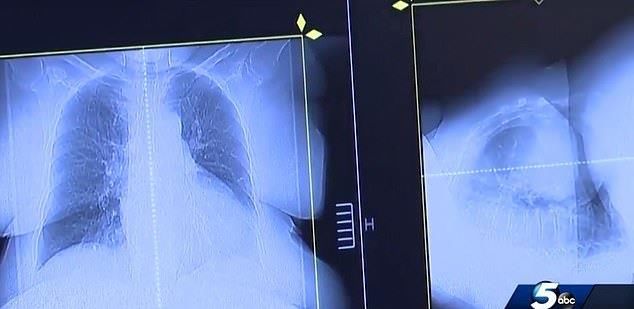

据英国《每日邮报》26日报道,一名来自美国的男子身患癌症晚期,就在他生命只剩三个月的时候,他遇到了一名兽医,兽医让他尝试用狗药来治疗癌症,

据英国《每日邮报》4月26日报道,一名来自美国的男子身患癌症晚期,就在他生命只剩三个月的时候,他遇到了一名兽医,兽医让他尝试用狗药来治疗癌症

服用狗药治好癌症是怎么回事?据英国《每日邮报》26日报道,一名来自美国的男子身患癌症晚期,就在他生命只剩三个月的时候,他遇到了一名兽医,兽医让他尝试用狗药来治疗癌